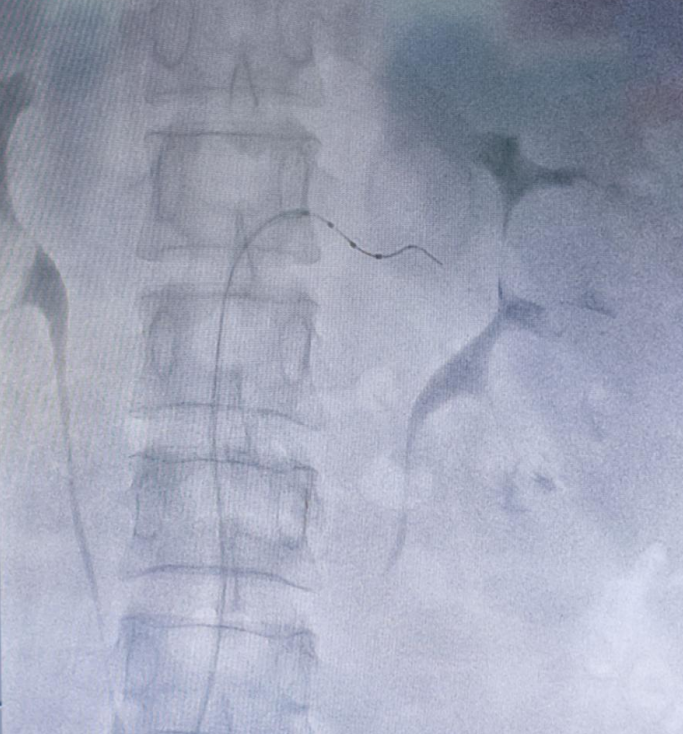

手术当天,张龙岩教授在副主任医师龚俊的配合下,麻醉后通过股动脉穿刺,沿指引导丝将消融导管分别送至双侧肾动脉以及各个分支,成功消融12次,30余个靶点。消融后无肾动脉痉挛、血管夹层、迷走神经亢进等不良反应,不到一个小时手术便成功完成。术后经过一天观察,患者血压即刻降至120/80mmHg。